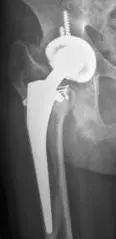

图2各种原因所致人工髋关节假体失败,需要行髋关节翻修术